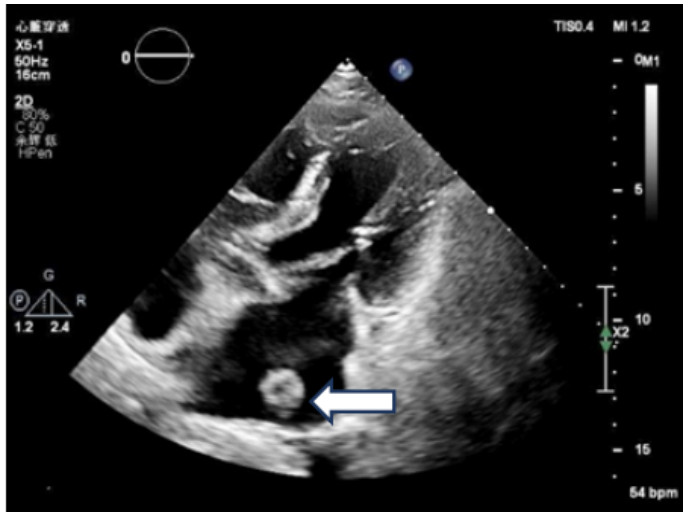

既往史:有高血压病史10年余,规律降压治疗,未监测血压。房颤病史2年余,2022年11月在本院超声心动图显示左心房见一不均质低回声团,位置随心动周期漂动(17 mm×16 mm)”(见图 1),左房前后径40 mm,左右径46 mm,上下径70 mm。LVEDD 39 mm,LVEF:60%。二尖瓣E峰0.92 m/s,最大压差3.39 mmHg(1 mmHg=0.133 kPa)。反流面积3.8 cm2,二尖瓣口频谱呈单峰。舒张期二尖瓣口前向血流,E < A,无舒张功能不全。进一步行经心脏超声造影提示:Flash后,左心室心腔内团块未见明显灌注(见图 2)。

| 注:左房内可见团块样回声影(箭头处),约17 mm × 16 mm 图 1 患者经胸腔超声心动图 |